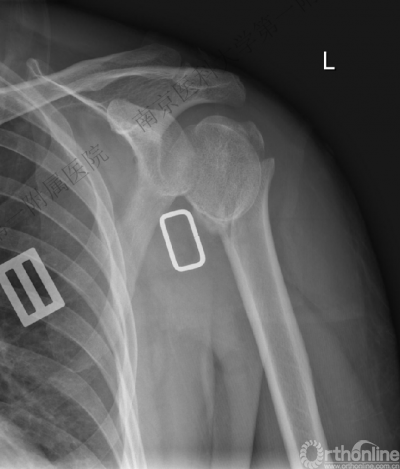

男性,48岁,坠落伤致左肩关节肿痛、活动受限1天。

术后肩关节X线正位片

Ⅲ型: +肱骨颈骨折+小结节骨折+大结节骨折(病例2),以骨折线向肱骨近端外侧壁延伸为另一特征。

五、反Hill-Sachs 损伤对肩关节稳定性的影响